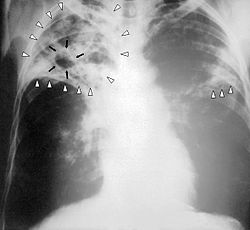

ويعتبر مرض السل الرئوي من الامراض القديمة تسببه بكتيريا تسمى الميكروبكتيريوم. وهو مرض معدي وينتقل من مريض الى أخر عن طريق الهواء.وبعضه عن طريق تناول أكل ملوث(كالألبان). وغالبا مايصيب الجهاز التنفسي(الرئتين ) وعلاجه يحتاج الى مدة تتراوح بين 6 اشهر الى سنة ونسبة نجاحه تبلغ 95% , 50% من مرضى السل يلقون حتفهم خلال 5 سنوات إذا تركوا بغير علاج ومعظم الباقين يصحبون في حالة صحية سيئة , واذا لم يعالج المصاب سيعدي من 5 – 10 اخرين .

وتذكر الاحصائيات ان 1% من سكان العالم يصاب سنويا والوفيات تصل الى 2,7 مليون شخص كل عام , اغلب مرضى السل تتراوح اعمارهم من 15 – 49 سنة , وهناك 900 مليون امرأة مصابة بالمرض في العالم , والمرض تسبب منذ عام 1882 ميلادي وحتى الان بوفات 200 مليون شخص , حيث يموت شخص واحد على الاقل كل 4 ثوان .